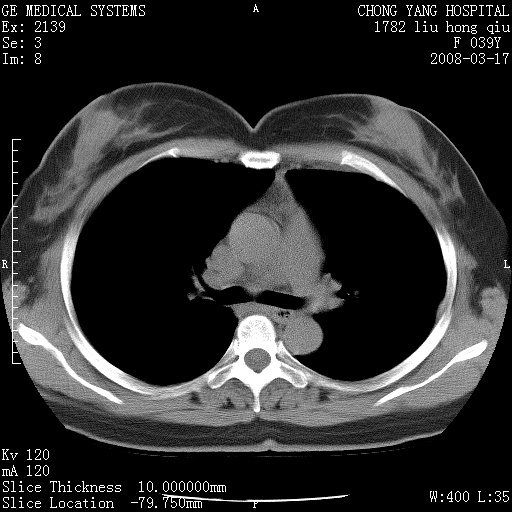

以下是引用yangxue121在2008-5-31 20:24:00的发言:[br]考虑多发胸膜间皮瘤[br]左侧少量胸腔积液[br]肝脏密度不均

以下是引用王仕学在2008-5-31 20:10:00的发言:[br]考虑胸膜间皮瘤。

以下是引用长城干红在2008-5-31 21:42:00的发言:[br]肝脏密度不均,建议增强扫描,胸膜下多发结节,考虑为胸膜来源的原发肿瘤或转移瘤。